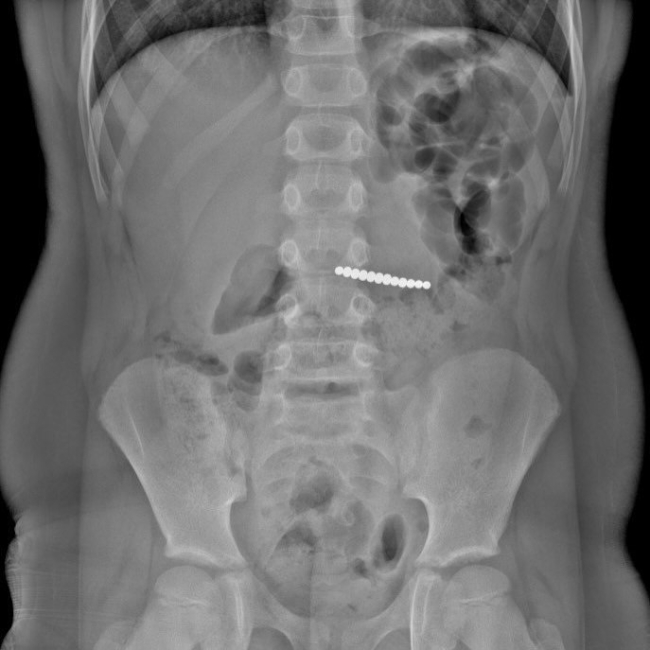

– Що бачили на рентгенах: з 29 по 31 травня— магніти у проєкції 3-4 поперекових хребців, залишались у тонкому кишечнику без змін протягом кількох діб. Це стало підставою для проведення ФГДС, щоб виключити затримку магнітів у шлунку чи дванадцятипалій кишці, – розповів лікар на своїй фейсбук-сторінці.

Далі магніти опустились у товстий кишечник, де сформували кільце поблизу прямої кишки: критичний момент виник на 11-й день. На щастя, обійшлося без операції – 10 червня усі магніти вийшли природним шляхом, без ускладнень.